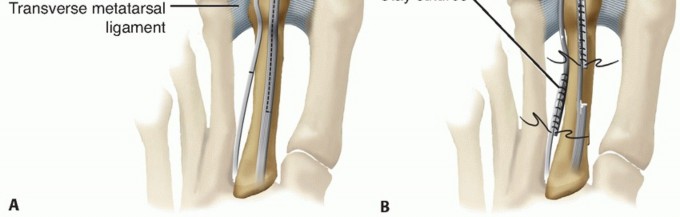

A long Z incision of the EDL is made, and the EDB is released at the distal metatarsal level (TECH FIG 4A).

- TECH FIG 4 • A. Long Z incision through the EDL tendon. EDB transected at the level of the distal metatarsal shaft. B. Correction of deformity and pinning. The distal EDL stump has been shuttled through the transverse drill tunnel and anastomosed to the proximal stump of the EDB tendon. The proximal stump of EDL has been repaired side to side with the distal stump of the EDB. (Adapted from Lui TH, Chan KB. Technique tip: modified extensor digitorum brevis tendon transfer for crossover second toe correction. Foot Ankle Int 2007;28:521-523.)

The distal stump of the EDL is passed through the bone tunnel from medial to lateral. The passed tendon is then shuttled from distal to proximal, plantar to the transverse metatarsal ligament between the second and third metatarsals.

The transferred tendon is tensioned, and a 0.062-inch K-wire is inserted across the MTP joint to hold the toe in a corrected position (TECH FIG 4B).

The distal stump of the EDL is then repaired side to side with the proximal stump of the EDB.

The proximal stump of the EDL is then sutured to the distal stump of the EDB in side-to-side fashion.